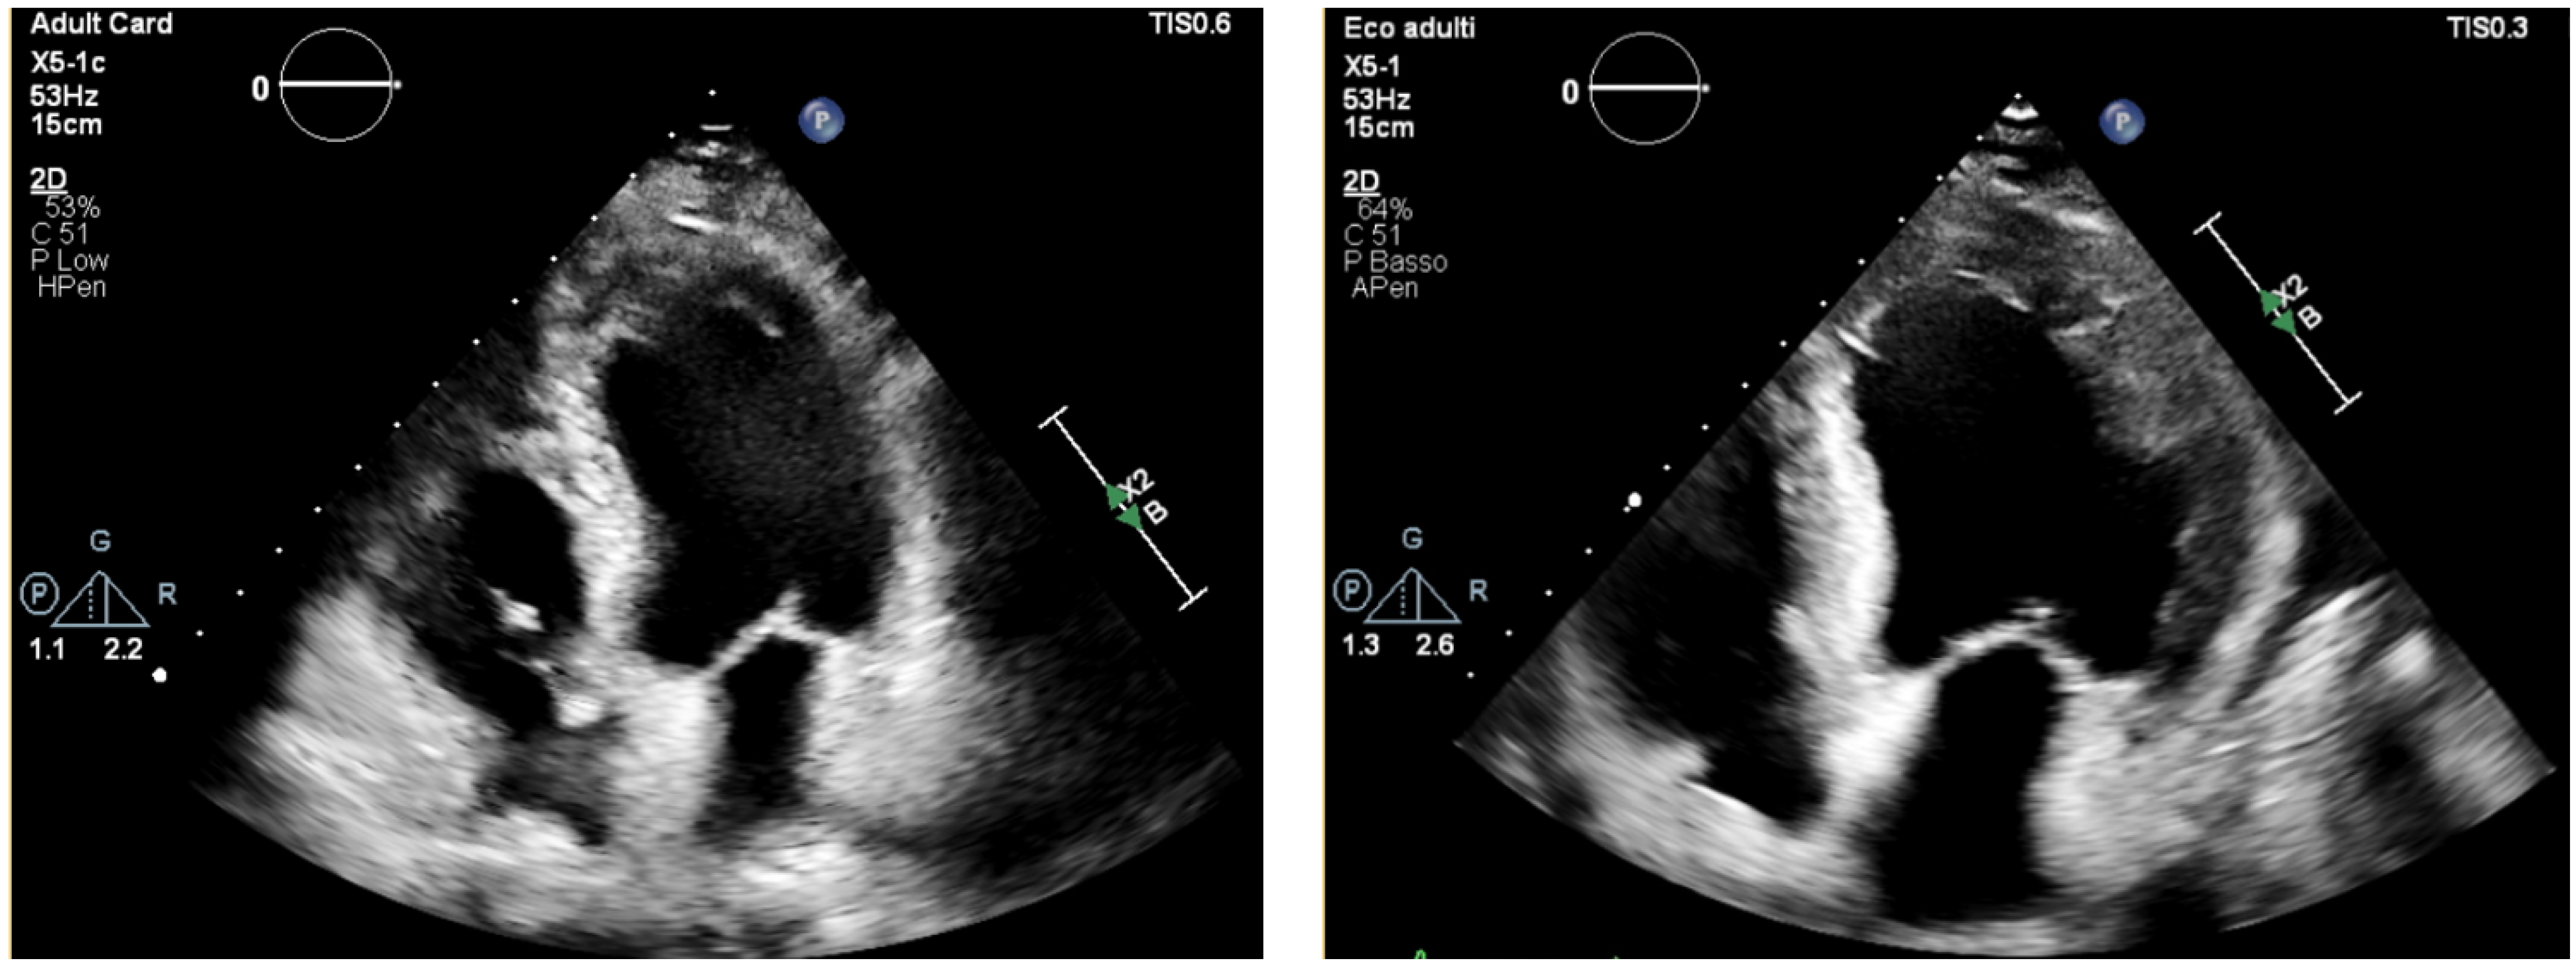

During the acute phase, TTE is important for assessing global cardiac function, through the left ventricular (LV) ejection fraction (EF). However, findings may be normal or slightly abnormal, such as hypokinesia, subendocardial hyperechogenicity, chamber dilation or increased wall thickness (pseudohypertrophy) [] (Figure 2).

Figure 2.

Transthoracic echocardiography, apical four-chamber view. Normal LV thickness and size (left), becoming pseudo-hypertrophic and hypokinetic after onset of eosinophilic myocarditis (right).